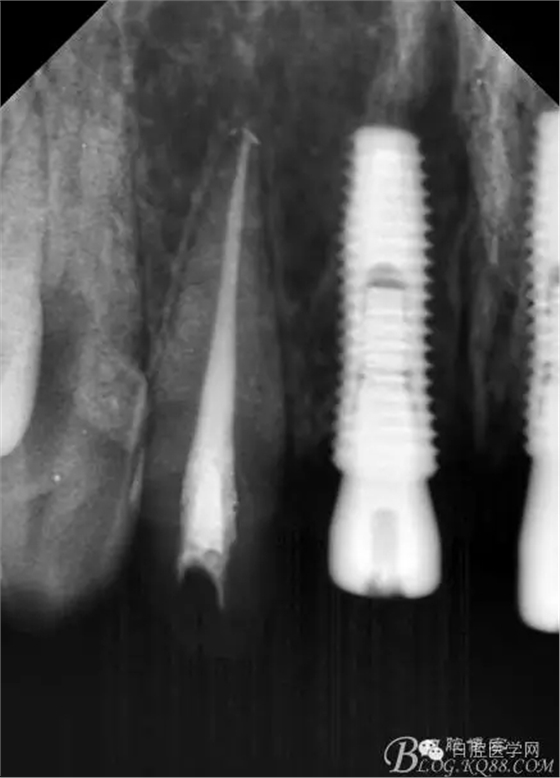

設(shè)計方案:11.21種植(選用登騰系統(tǒng),GBR植骨)12.22 RCT后樁冠修復(fù),牙齦瓷修復(fù)。

一期手術(shù)后3-6個月可做二次修復(fù),接愈合基臺,拆線后10-15天根據(jù)情況可以采模型做牙冠。